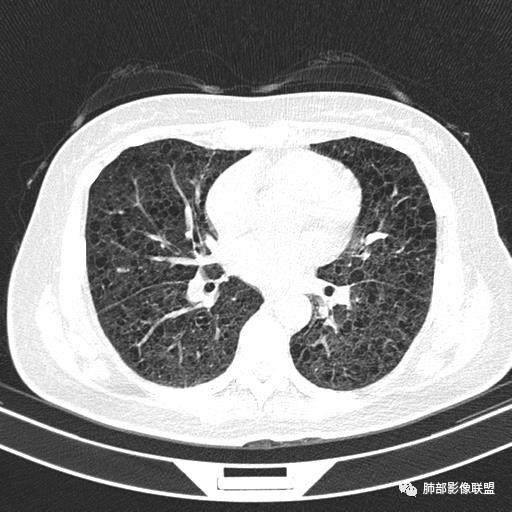

双肺弥漫囊腔,累及肋膈角,囊腔形态相对规则单一。

CT平扫示双肺弥漫分布大小不等囊状薄壁透光区,无内、中、外带分布差异,间质稍示增厚。拟LAM

中年女性,双肺弥漫性磨玻璃密度影,并见弥漫性分布大小不一囊腔,壁薄,形态规则,考虑lam,鉴别苯中毒肺损伤致间质改变

中年育龄期女性,双肺多发含气囊腔弥漫性分布,囊间肺组织结构正常,常规考虑Lam

双肺多发大小相近的囊状影,分布趋势趋于一致,中年女性,考虑LAM。部分囊内见血管及分隔影,小叶中心性肺气肿代排

CT表现:双肺弥漫大小不等的薄壁囊腔,囊壁<2mm,外形规则,血管影多位于囊腔周围,囊腔之间肺组织正常,随着疾病进展到晚期,囊腔变大、增多,不可胜数,囊腔可融合成较大的囊,与肺气肿相似,形成间质性肺纤维化。部分病例可出现结节影。